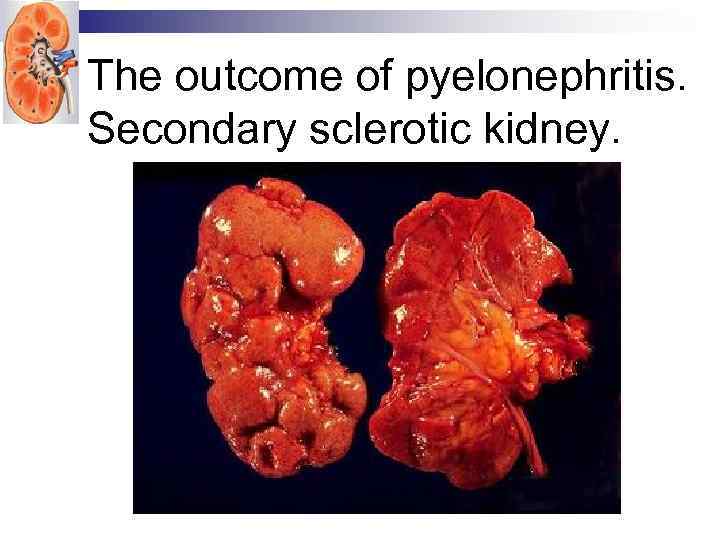

The outcome of pyelonephritis. Secondary sclerotic kidney.

The outcome of pyelonephritis. Secondary sclerotic kidney.